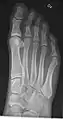

- Foot / Toes - Dorsoplantar, Oblique and Lateral.[19]

Normal right foot by dorsoplantar projection

Oblique projection

Lateral projection